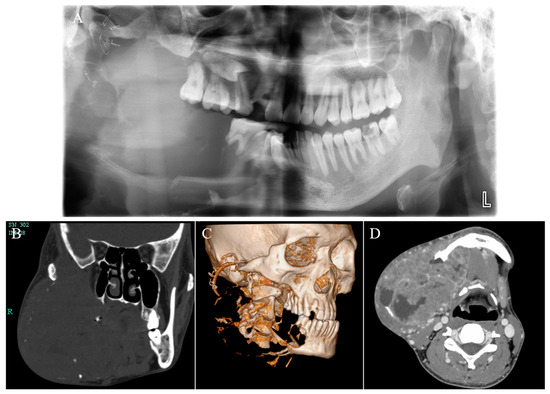

Giant Mandibular Ameloblastoma with Rare Hypercalcemia: A Case Report and Literature Review

by Wenyi Shen, Chenlu Xu, Pan Wang, Junpeng Chen, Dan Yu and Huiyong Zhu

Medicina 2023, 59(11), 1956; https://doi.org/10.3390/medicina59111956 - 6 Nov 2023

Ameloblastoma is the most common benign odontogenic tumor with local invasion and high recurrence, which generally occurs in the jaw bones. Hypercalcemia is a common paraneoplastic syndrome that is commonly observed in patients with malignancies but rarely encountered in patients with benign tumors. Thus far, not many cases of ameloblastoma with hypercalcemia have been reported, and the pathogenic mechanism has not been studied in depth. This paper presents a case report of a 26-year-old male diagnosed with giant ameloblastoma of the mandible, accompanied by rare hypercalcemia. Additionally, a review of the relevant literature is conducted. This patient initially underwent marsupialization, yet this treatment was not effective, which indicated that the selection of the appropriate operation is of prime importance for improving the prognosis of patients with ameloblastoma. The tumor not only failed to shrink but gradually increased in size, accompanied by multiple complications including hypercalcemia, renal dysfunction, anemia, and cachexia. Due to the contradiction between the necessity of tumor resection and the patient’s poor systemic condition, we implemented a multi-disciplinary team (MDT) meeting to better evaluate this patient’s condition and design an individualized treatment strategy. The patient subsequently received a variety of interventions to improve the general conditions until he could tolerate surgery, and finally underwent the successful resection of giant ameloblastoma and reconstruction with vascularized fibular flap. No tumor recurrence or distance metastasis was observed during 5 years of follow-up. Additionally, the absence of hypercalcemia recurrence was also noted. Full article

Show Figures

Figure 1